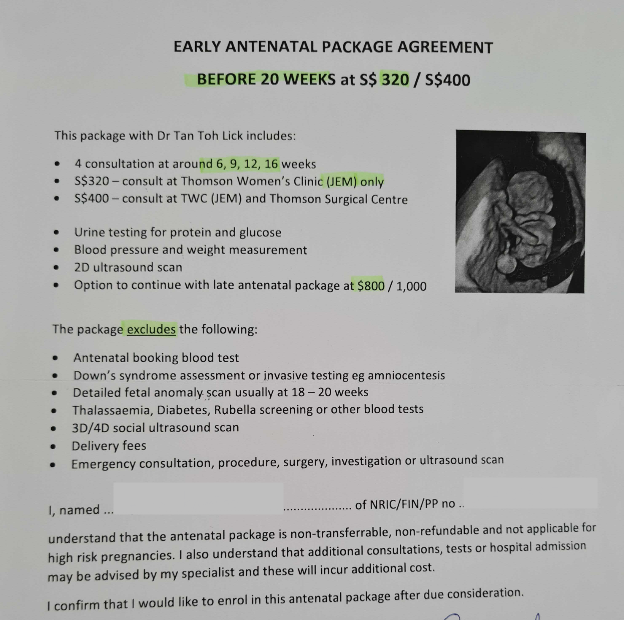

~病院のパッケージ~

心拍も確認できたということで

今後も同じ病院に通うならパッケージ購入した方がお得ということで

パッケージの説明を受けました。

Thomson Women's Clinic は多くのブランチがあるので、

同じ病院に通うか、他のブランチに行くかでパッケージの値段も変わるそうです😅

私はJEMブランチから変更の予定はなかったので

S$320のパッケージを購入しました😊

~本日のお会計~

今回から増えたサプリメントは

Dhaxtra softgel

脳の機能や正常な成長に必要なサプリメント(Fish Oil)

食事だけではなかなか必要な栄養素を取っていくのは難しそうなので

サプリも一緒に飲んで赤ちゃんに栄養届けていきたいと思います😉